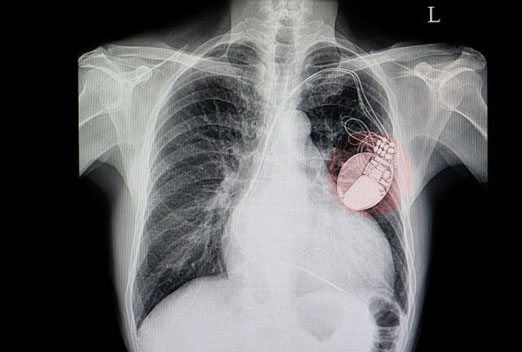

We have a some latest projects photos and Videos. this gallery explain different

health issues related to heart and more information for heart patients thats ill we help for your health improve.